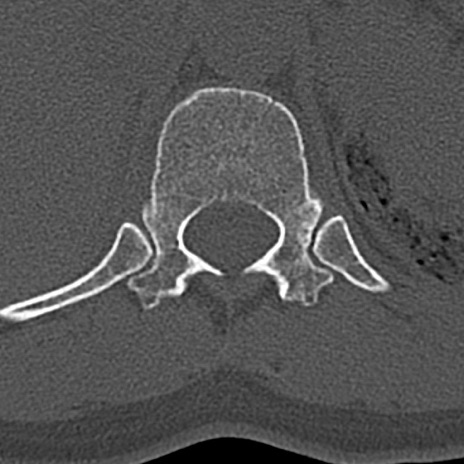

腰椎CT

横断像と矢状断像